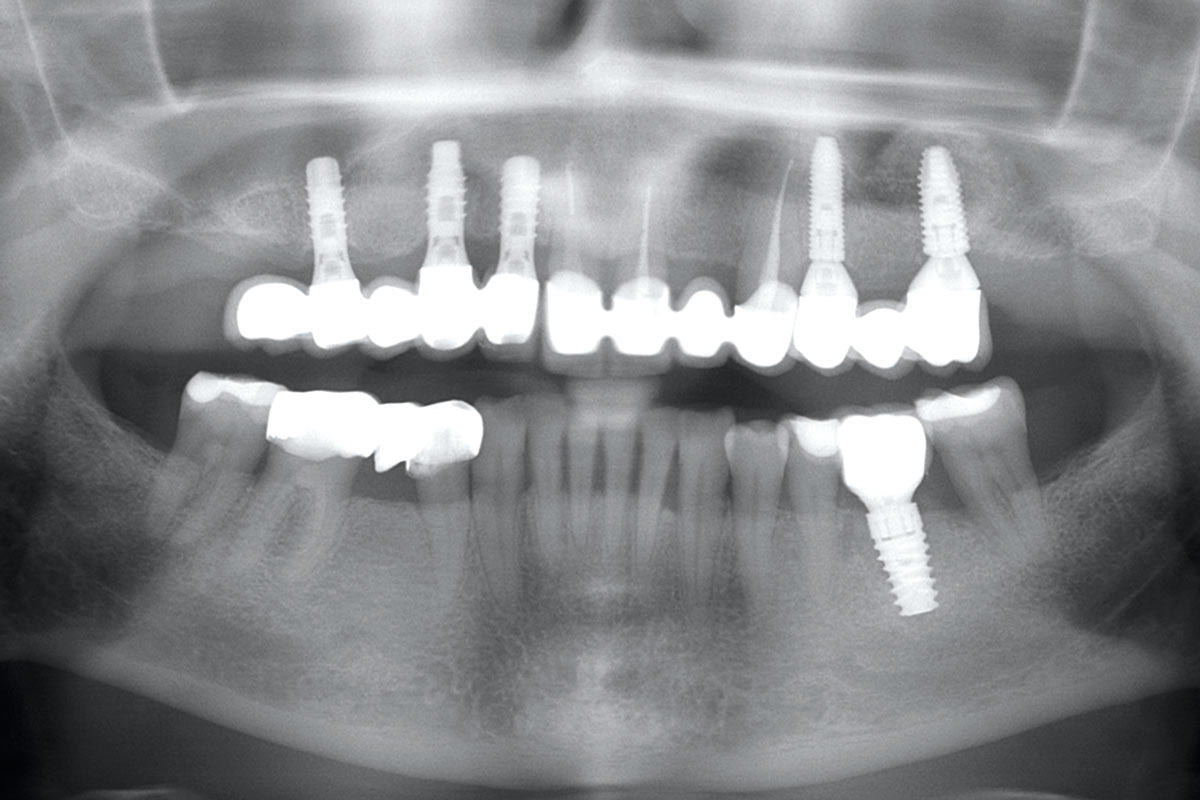

X-ray control before tooth extraction